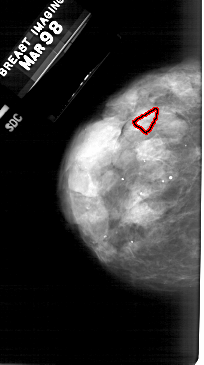

A_1484_1.LEFT_MLO

LEFT_MLO LINES 5491 PIXELS_PER_LINE 3271 BITS_PER_PIXEL 12 RESOLUTION 43.5 OVERLAY

FILE: A_1484_1.LEFT_MLO.OVERLAY

TOTAL_ABNORMALITIES 1

ABNORMALITY 1

LESION_TYPE CALCIFICATION TYPE PLEOMORPHIC DISTRIBUTION LINEAR

ASSESSMENT 4

SUBTLETY 1

PATHOLOGY BENIGN

TOTAL_OUTLINES 1

BOUNDARY